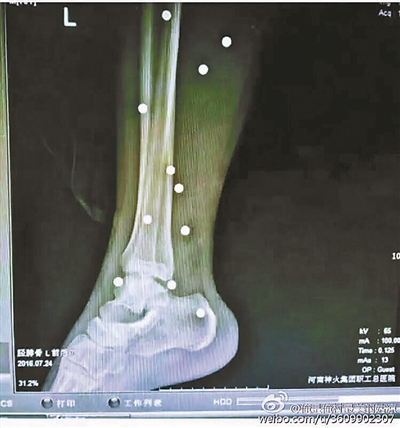

傷者體內(nèi)取出的鋼珠

爆炸導(dǎo)致鋼珠遍布傷者身體各處

黃明的伯伯對(duì)北青報(bào)記者表示,由于黃明直接踩到了爆炸物,所以傷情最為嚴(yán)重,“他的腿被炸斷,身體內(nèi)被炸進(jìn)了40多顆鋼珠。手術(shù)后已經(jīng)從體內(nèi)取出29顆鋼珠,還有十多顆鋼珠沒有取出來。”根據(jù)黃明的入院記錄,他全身有多處爆炸傷,且全身多處異物存留。